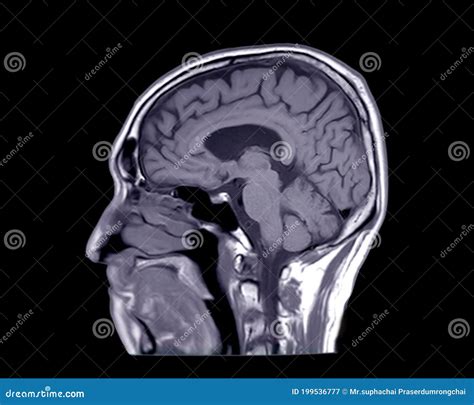

Understanding the intricacies of medical imaging is crucial for healthcare professionals, and one of the most informative views in this field is the Brain Sagittal View. This view provides a side-to-side perspective of the brain, offering insights into the structure and function of various brain regions. By examining the brain from this angle, medical professionals can diagnose and treat a wide range of neurological conditions more effectively.

The Brain Sagittal View is a medical imaging technique that presents a vertical section of the brain, dividing it into left and right halves. This view is particularly useful for visualizing the midline structures of the brain, such as the corpus callosum, the brainstem, and the cerebellum. By examining these structures, healthcare providers can gain a comprehensive understanding of the brain’s anatomy and identify any abnormalities or pathologies.

Interpreting the Brain Sagittal View requires a thorough understanding of brain anatomy and the ability to identify normal and abnormal structures. Key areas to focus on include:

• Corpus Callosum: This structure connects the left and right hemispheres of the brain and is crucial for communication between the two sides.

• Brainstem: This region controls many of the body’s automatic functions, such as breathing and heart rate.

• Cerebellum: Located at the back of the brain, the cerebellum plays a role in motor control, coordination, and balance.

• Ventricles: These fluid-filled spaces within the brain can indicate the presence of conditions like hydrocephalus if they are enlarged.

When interpreting the Brain Sagittal View, it is important to compare the images with normal anatomical references to identify any deviations or abnormalities. Radiologists and neurologists use their expertise to detect subtle changes that may indicate the presence of a neurological condition.

Sagittal View Vertical section dividing the brain into left and right halves Corpus callosum, brainstem, cerebellum